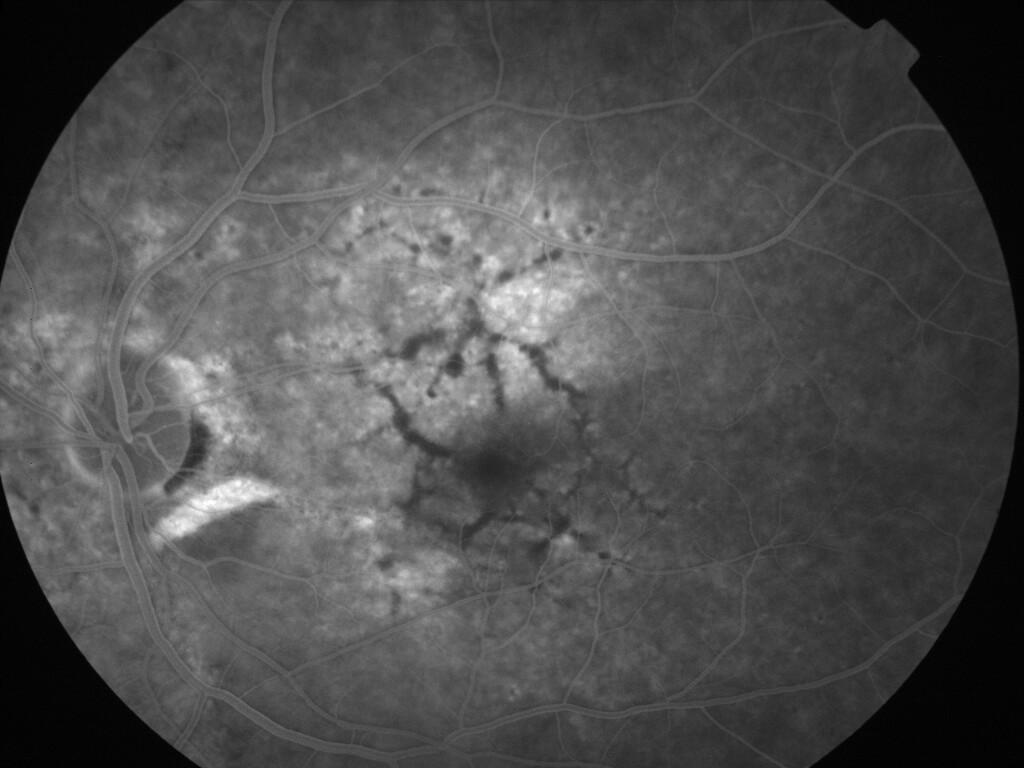

ASSOCIATION STRIES ANGIOIDES ET DYSROPHIE MACULAIRE RETICULEE

NEOVASCULARISATION